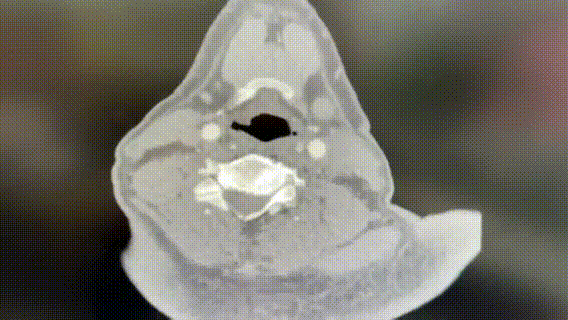

影像学排除大面积脑梗死;

分析远端管腔塌陷程度及病变成分;

确认残端形态及远端颅内血流